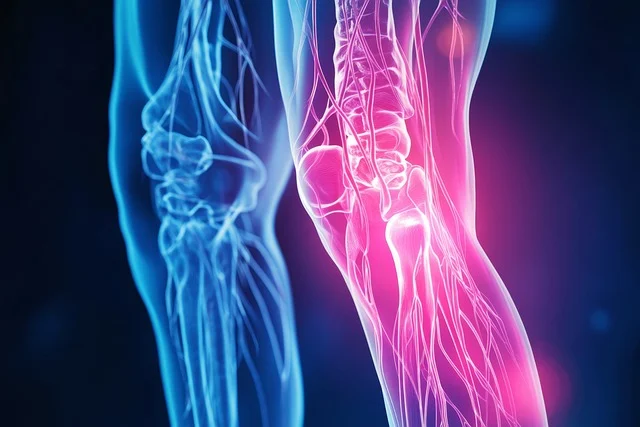

이번 포스트에서는무릎통증 원인 증상 총정리 하여 자히 알아보고, 이를 예방하고 관리하는 방법을 소개하고자 합니다. 아시다시피 무릎통증은 다양한 원인으로 발생할 수 있으며, 일상 생활에 큰 불편을 초래할 수 있습니다. 저도 무릎통증때문에 꽤나 고생한 적이 있었는데요. 무릎통증에 대한 올바른 이해는 효과적인 치료와 예방의 첫걸음이라고 생각합니다. 우리 같이 무릎통증 원인 과 증상에 대해 자세히 알아보도록 하시죠.

무릎통증 증상

무릎통증 증상 - 통증 무릎 통증은 다양한 형태로 나타날 수 있으며, 움직일 때나 휴식 중에도 발생할 수 있습니다. 통증은 급성 또는 만성일 수 있으며, 무릎의 특정 부위에 국한되거나 넓게 퍼질 수 있습니다.